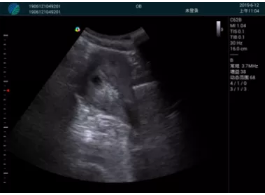

M20查看:囊內(nèi)回聲均勻,邊界清晰,囊壁光滑

M20引導(dǎo)抽吸術(shù)后囊腫消失,原區(qū)域空腔形成,脂肪層與腺體層架構(gòu)發(fā)生改變

超聲以操作簡(jiǎn)單、定位準(zhǔn)確、實(shí)時(shí)顯像、費(fèi)用低廉等優(yōu)勢(shì),而成為麥默通乳腺活檢治療乳腺腫塊最常見的引導(dǎo)手段,已逐步在各大醫(yī)院開展此類手術(shù)。

2、超聲的可視化操作,能準(zhǔn)確的顯示病灶的位置、最大徑,選擇合適的刀具,決定切口的位置和方向,避開血管、減少出血危險(xiǎn)并實(shí)時(shí)觀察乳腺病灶的切割情況,避免造成腫塊組織殘留